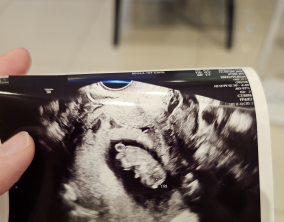

임신 수치 16, 9주차 기적의 기록